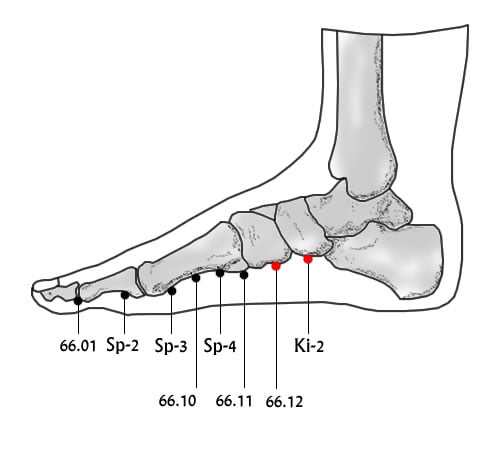

מיקום

1 צון פוסטריורית ל- 66.11.

Dr Wei Chieh Young ממקם את הנקודה באותו המיקום של Ki-2 קרובה לעצם.

Li Guo Zheng הנקודה נמצאת דיסטלית ל Ki-2.